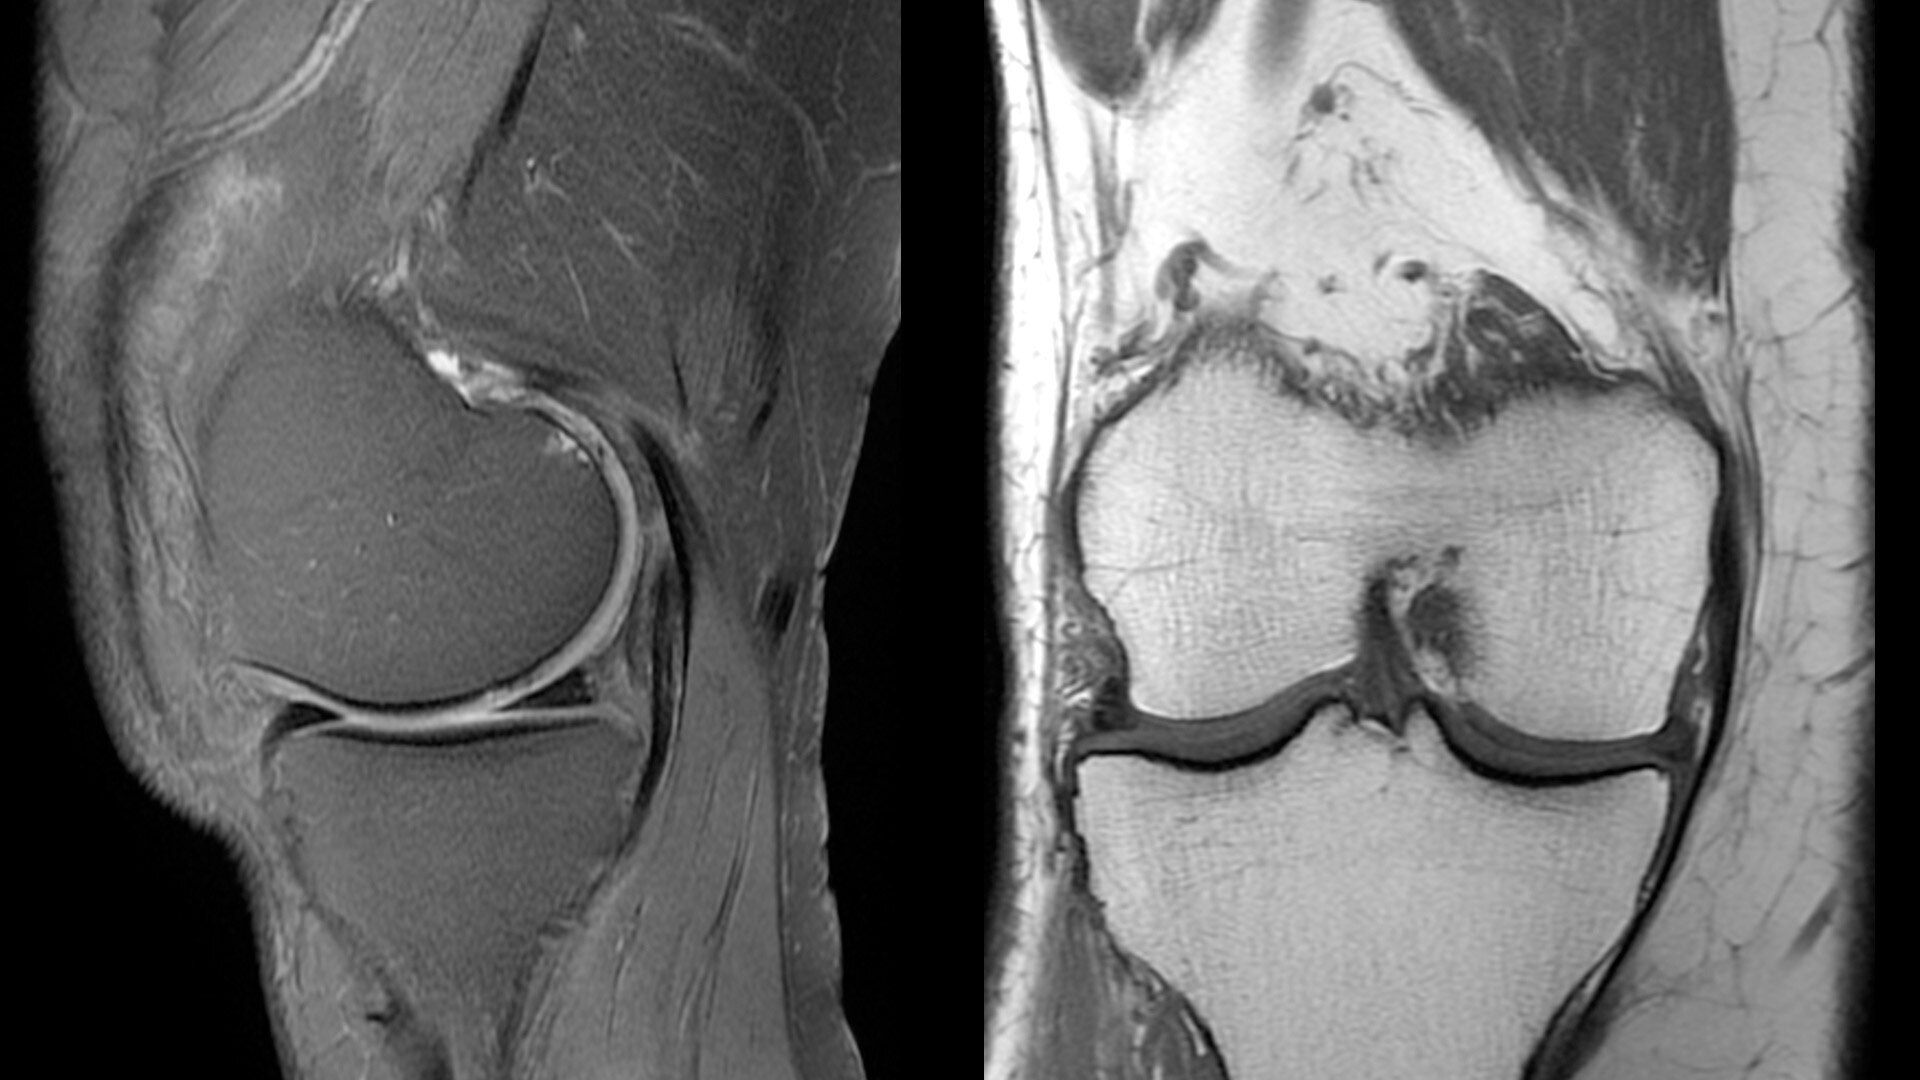

The shape of the MRI coil no longer determines what you can do with it. Wrap it around a knee for a complete knee image. Drape it over the patient's body. With an adaptive AIR™ Coil that is light, form fitting and easy to position, it’s the closest you can get to total positioning freedom with 360-degree coverage.

• 360 degrees of coverage for MSK imaging

• Positioning freedom with previously hard-to-scan anatomies